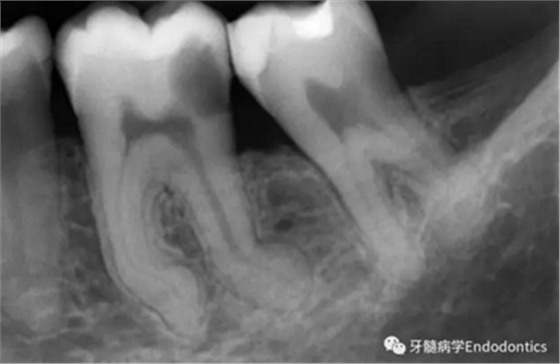

圖2.疏通根管冠方2/3后,使用次氯酸鈉溶液沖洗根管,且可以使用手用器械、GG鉆(刷洗動作)、旋轉(zhuǎn)鎳鈦成形銼預(yù)敞根管。當(dāng)冠方2/3進(jìn)行了合適的預(yù)備且充滿沖洗液后,接著進(jìn)行根尖1/3的探查以收集信息。使用小的手用銼(8號或10號K銼)疏通根管的剩余部分,確認(rèn)建立了流暢的、無阻礙的、平滑的到達(dá)根尖止點(diǎn)的引導(dǎo)通道。

圖3.存在細(xì)小狹長、可能多維的復(fù)雜根管解剖時(shí),使用10號K銼不可能立即疏通根管到達(dá)根尖止點(diǎn)。隨后醫(yī)生應(yīng)嘗試使用更小的銼探查以達(dá)到根尖。但是,通常不需要使用6號和8號K銼對到達(dá)根尖的引導(dǎo)通道進(jìn)行擴(kuò)大,除非是特別困難的病例。